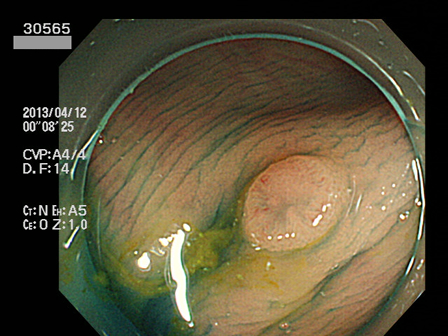

上記100名より抽出した平坦・陥凹型腺腫(=癌化の危険が高いが見落としやすい病変)の内視鏡写真

30500 30502 30504 30506 30510 30512 30513 30519 30520 30521 30523 30524 30526 30529 30530 30532 30533 30534 30535 30540 30543 30545 30546 30548 30551 30552 30554 30555 30558 30560 30561 30562 30564 30565 30568 30571 30572 30573 30574 30575 30576 30583 30584 30585 30586 30587 30588 30591 30592 30593 30596 30597・・・・・・の52名